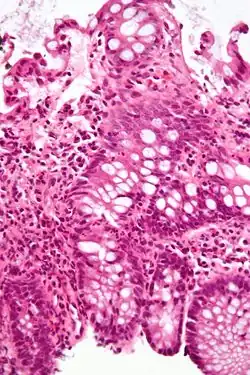

A micrograph demonstrating cryptitis, a microscopic correlate of colitis. H&E stain.

An important investigation in the assessment of colitis is biopsy for histopathology. A very small piece of tissue (usually about 2mm) is removed from the bowel mucosa during endoscopy and examined under the microscope by a histopathologist. A biopsy report generally does not state the diagnosis, but should state any presence of chronic colitis, give an indication of disease activity, as well as state the presence of any epithelial damage (erosions and ulcerations).[6]